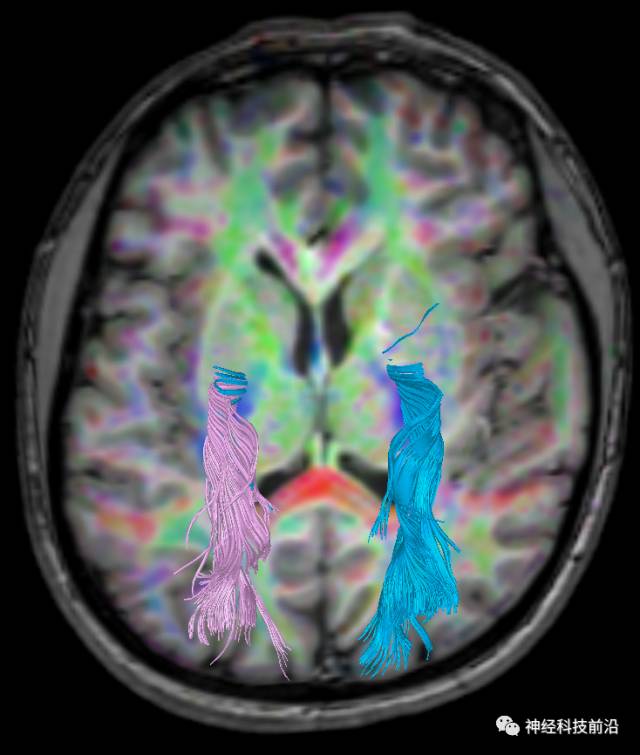

下面为皮质脊髓束的走形及位置